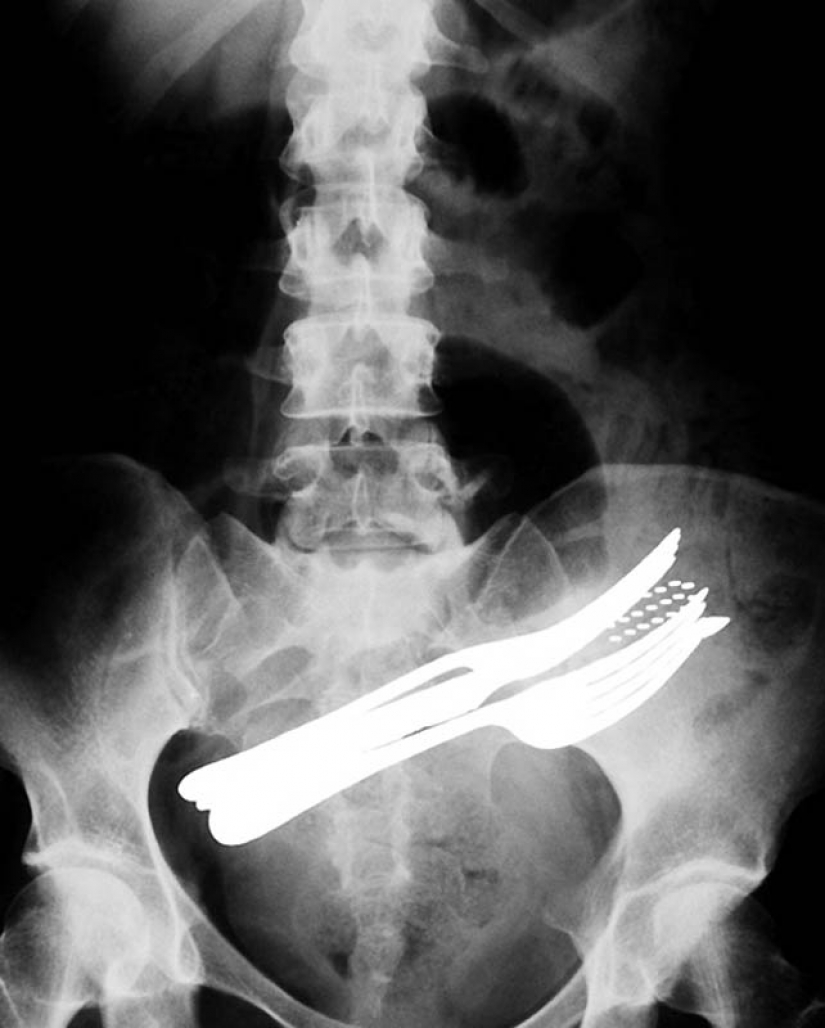

2. El estómago de un paciente que ingiere dos tenedores, un bolígrafo y un cepillo de dientes.